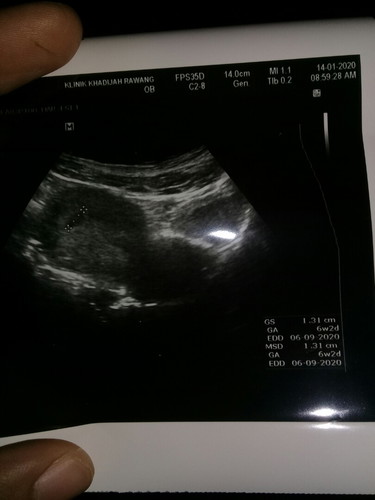

Td dah g scan alhamdulillah bby ok kantung cantik bulat bru 6w 2d rupanya , normal x 6w bru implantation bleeding? lg seminggu appointment repeat scan hrp2 la spotting niy kejab jer• dr bg ubat kuatkan rahim utk seminggu